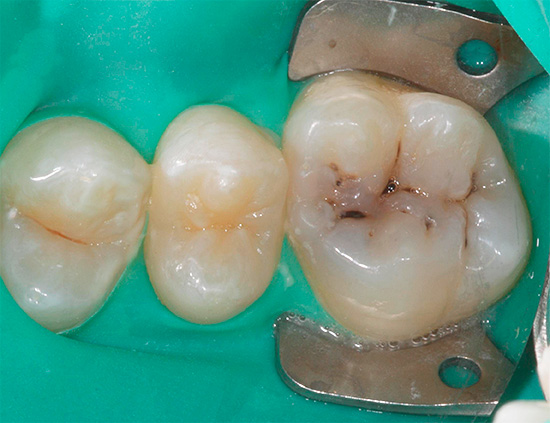

Ad esempio, di seguito nella foto - carie delle fessure. Sui denti, appare sulla superficie masticatoria nelle depressioni naturali chiamate ragadi. In alcuni casi, le linee nere sono così piccole che la sonda dentale e lo sguardo del medico non indugiano su di esse, ma spesso il problema è chiaramente visibile ad occhio nudo:

La carie da fessura è pericolosa perché vaste aree della dentina colpita possono essere nascoste sotto danni allo smalto apparentemente minori. Per una migliore comprensione, guarda un video che mostra schematicamente come la carie penetra nei tessuti dei denti profondi:

E poi nella foto: la cavità orale con i denti colpiti dalla carie delle fessure. Linee scure visibili, sebbene non grandi, ma chiaramente visibili sui molari. L'installazione di otturazioni qui non può più essere evitata, ma è del tutto possibile prevenire lo sviluppo della pulpite.